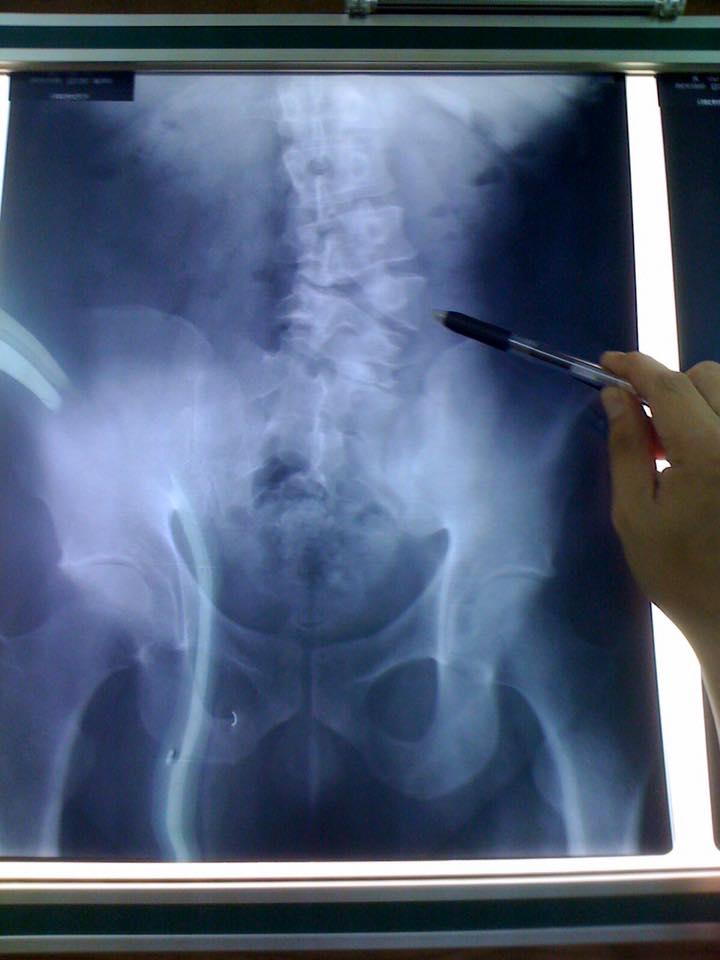

え?

背骨が

無い?

「あー、そういう事ね!背骨が欠けてると

いうか写真の通り奇形があるということね」

背骨が無いんです!にはぶったまげたけど

結構こういう奇形のひとは頻繁にいるんだ。

例えばレントゲンも撮らないでこんな

棘突起を辿って矯正をしたとする。

非常におっそろしい結果が待ってますねきっと。

見つけやすすぎる腰椎の歪み

レントゲンも見せられてもうね、

スゲ~~~!興味深くて。